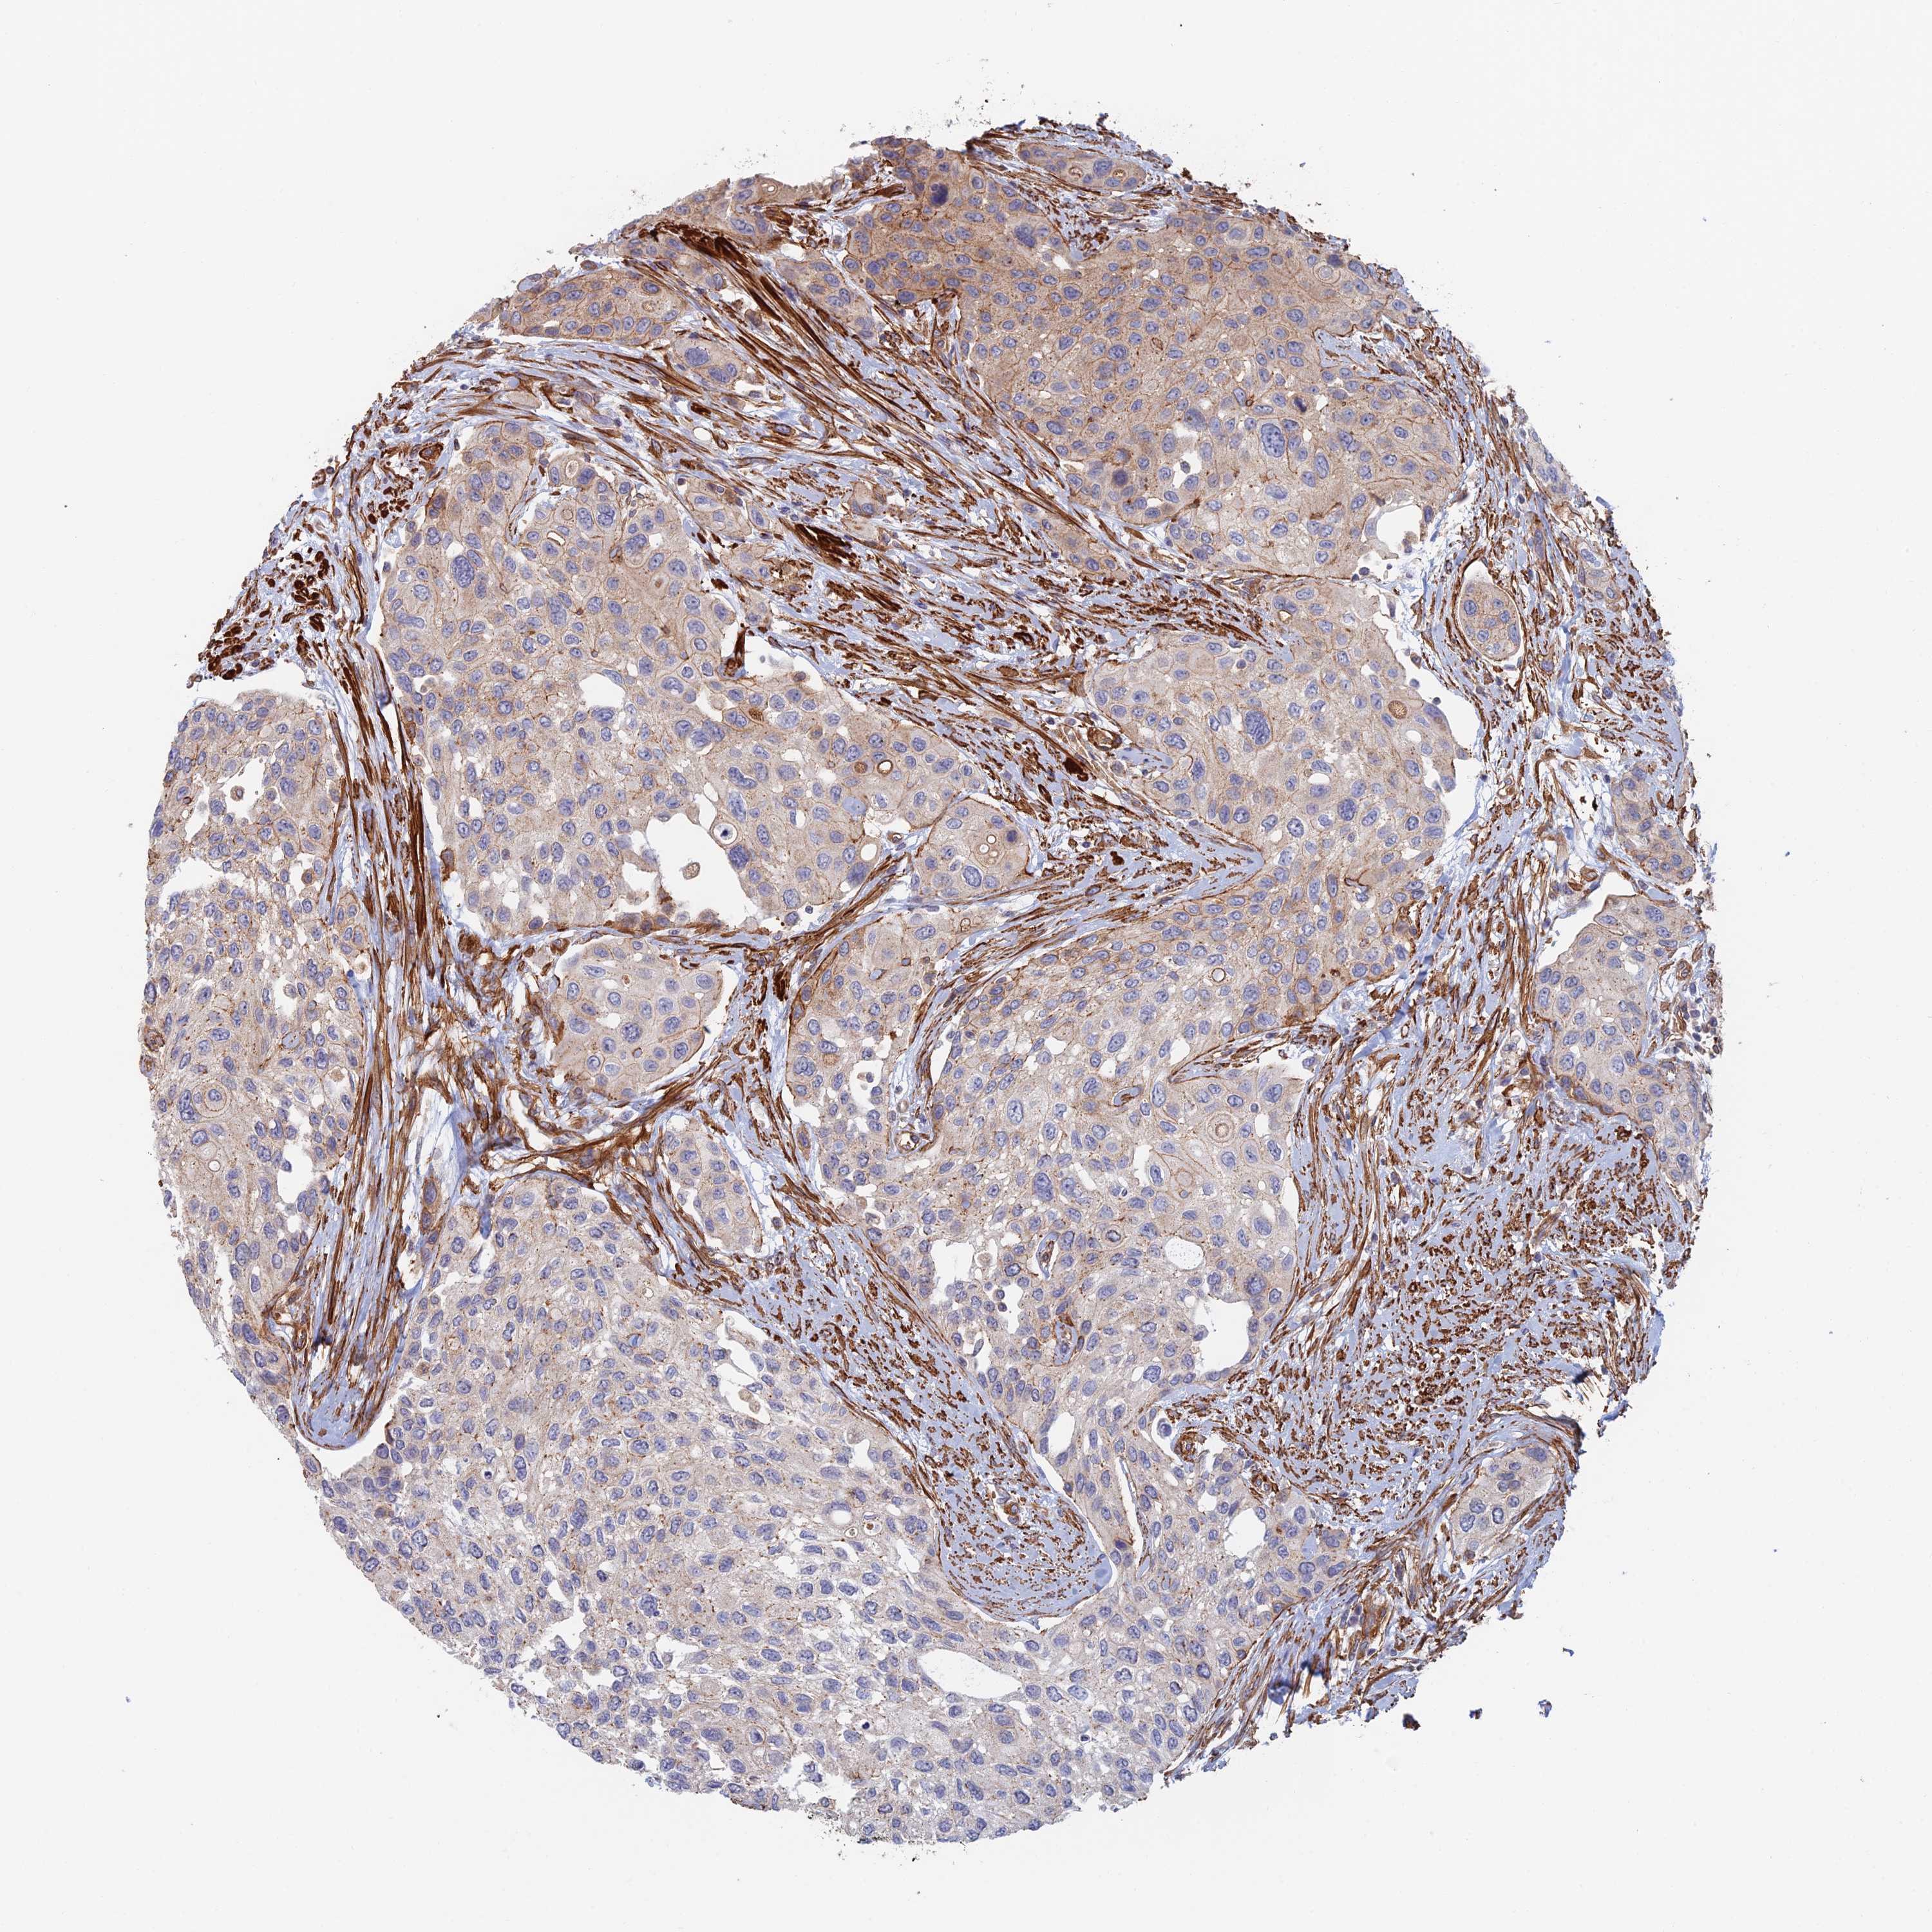

UROTHELIAL CANCER - Protein expressioni

A mouse-over function shows sample information and annotation data. Click on an image to view it in a full screen mode. Samples can be filtered based on level of antibody staining by selecting one or several of the following categories: high, medium, low and not detected. The assay and annotation is described here.

Note that samples used for immunohistochemistry by the Human Protein Atlas do not correspond to samples in the TCGA dataset.

Antibody stainingi

Antibody staining in the annotated cell types in the current human tissue is reported as not detected, low, medium, or high, based on conventional immunohistochemistry profiling in selected tissues. This score is based on the combination of the staining intensity and fraction of stained cells.

Each image is clickable and will lead to virtual microscopy that enables deeper exploration of all samples and also displays staining intensity scores, fraction scores and subcellular localization as well as patient and tissue information for each sample.

Antibody CAB025747

Antibody CAB044670

Staining

High

Medium

Low

Not detected

Intensity

Strong

Moderate

Weak

Negative

Quantity

>75%

75%-25%

<25%

None

Location

Nuclear

Cytoplasmic/membranous

Cytoplasmic/membranous,nuclear

Urothelial carcinoma, Low grade

Urothelial carcinoma, High grade